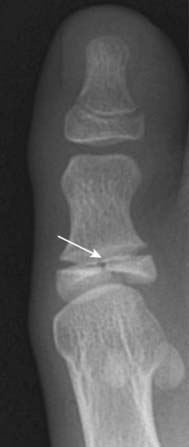

Figure 22-5 Dislocation and subluxation.

A, In a dislocation, the bones that originally formed the two components of a joint are no longer in apposition to each other (solid white arrows). The terminal phalanx is dislocated lateral compared to the middle phalanx. B, In a subluxation, the bones that originally formed the two components of a joint are in partial contact with each other. The humeral head (H) is subluxed inferiorly (solid white arrow) in the glenoid (G) because of large hematoma in the joint secondary to a fracture of the humeral neck (solid black arrow). The hematoma itself is not visible by conventional radiography.